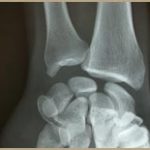

The doctor usually prescribes additional tests. These are mainly X-rays. Two x-rays are usually taken, showing the wrist from the front and the side. If the X-ray is not precise, or if the lesion is complex, the doctor may opt for a CT scan. This enables all the bones to be observed and their position precisely determined.